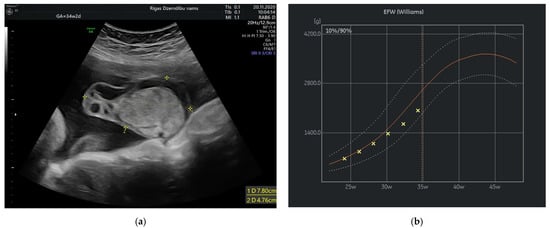

The size of the solid component was 3.4 × 2.3 cm and did not change during the pregnancy. The umbilical arteries and vein were running around and through, extra vessels were not observed in the tumor (Figure 2a). At the follow-up, the mass had rapidly enlarged in the size, from 285.32 cm3 at 26 weeks to 1929.36 cm3 at 32 weeks (Figure 2b). As well the reduction of fetal growth was observed from 30th week of gestation (Figure 3b).

Figure 2.

(a) Umbilical vessels going through the tumor at 32 + 2 weeks by 3D static HD flow (glass mode) imaging; (b) Tumor appearance at 32 + 2 weeks.

The latest development of high-resolution ultrasound machines and 3D technology yields diagnostic accuracy of umbilical cord anomalies such as true knots, cord aneurysms, cysts, hematomas, excessive/ absent coiling, true cord tumors etc. [11,12,13]. Volume acquisition of the vessels by static 3D in combination with color Doppler can be used to assess angioarchitecture and differentiate vascular malformations applying different displays, including glass-body mode, when blood flow can be visualized together with the surrounding structures [14]. In our case the tumor was detected by 2D mode and additional application of the high definition (HD) flow Doppler allowed to delineate the course of blood vessels, their coiling and blood flow within the tumor. High resolution images may provide auxiliary information to the real 2D ultrasound, therefore facilitate management, patient consultation and even prognostication.